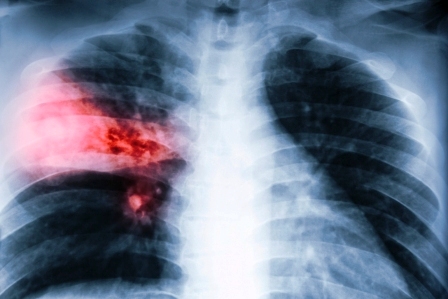

- Udržiava zdravé dýchacie cesty

- Eliminuje kašeľ, dusenie a hlieny